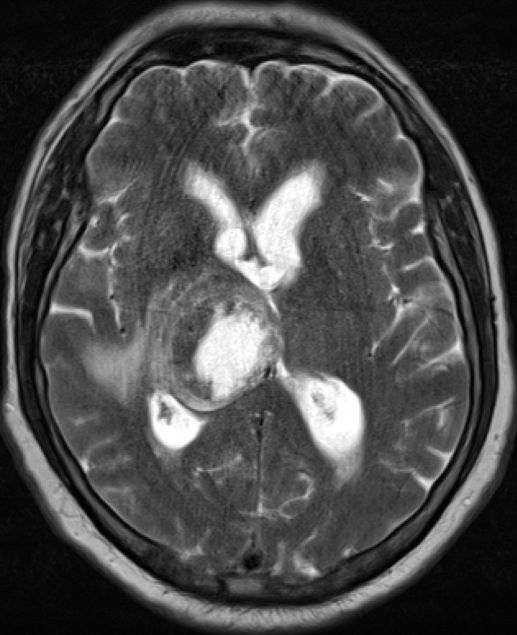

| Thalamus | 59jähriger Patient mit schlecht differenziertem

Adenokarzinom des linker Oberlappens cT2b pN1 M1b (pul, bra). Latente

Armparese links und Feinmotorikstörung der linken Hand. Keine

Sensibilitätsstörung, Sprachstörung, kognitive Defizite. Große Metastase in

rechten Thalamus.![]() | |||